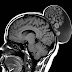

Casos Clínicos: Mujer de 52 años con hinchazón indolora del cuero cabelludo.

Un colega, de Ambato, Ecuador, que desarrolla su trabajo en Buenos Aires, Argentina, envía estas imágenes con el siguiente texto: Buenas...